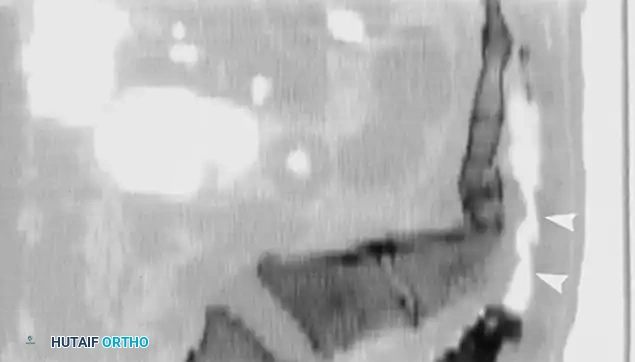

A

B

C

Fig. 35-62 A, Sagittal CT scan of transverse fracture through S3 resulting in transection of sacral nerve roots (arrow) . B, MRI of sacral fracture resulting in complete canal compromise. C, Postoperative CT scan shows decompression of sacral spinal canal after laminectomy (arrows) .